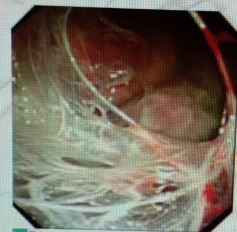

蜘蛛网胸水(包裹性胸腔积液),在胸腔镜下是什么鬼样子的呢?

且看胸腔镜:

胸腔里面这么多分隔,你能保证你的针在哪个小分隔里面?除非你有孙悟空的火眼金睛!

在胸腔镜下,是“蜘蛛网+蜂窝状”般的变态存在。

你说说,这种情况怎么愉快的抽胸水?